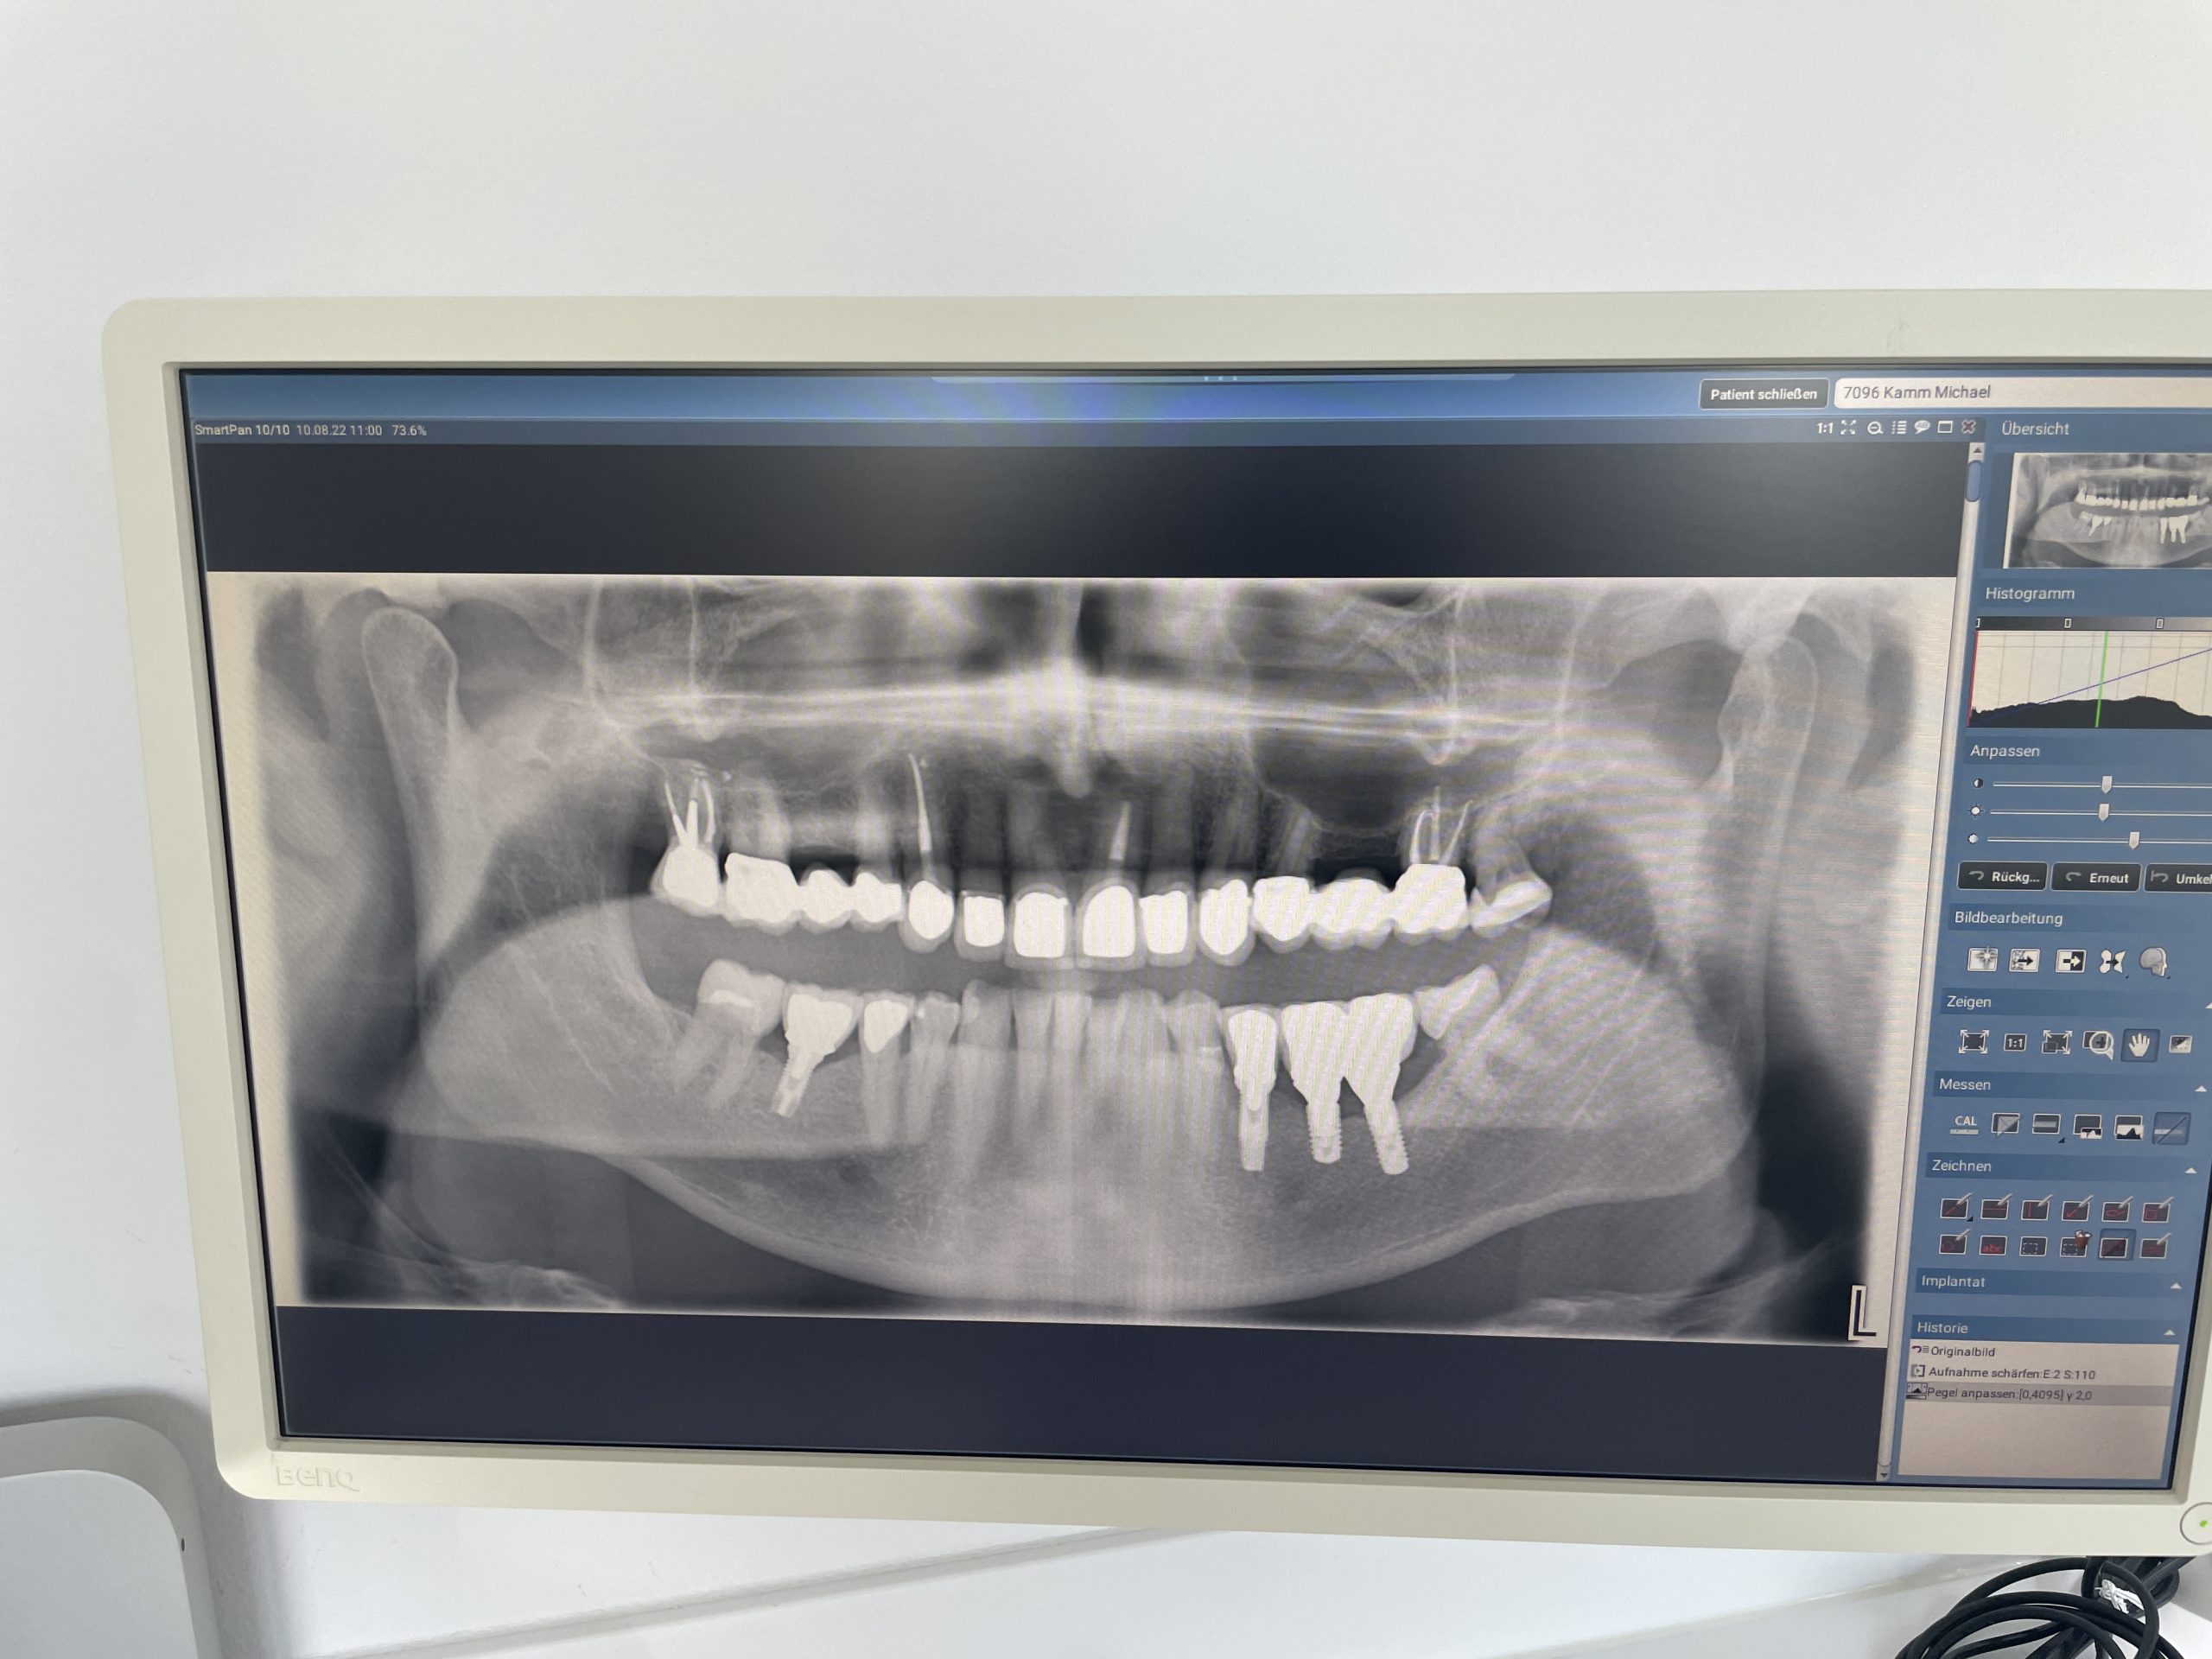

Die zweite Septemberwoche verbringe ich allein in München, da Annette ihr On-Boarding bei Pomellato in Mailand absolviert. Nach einer intensiven Arbeitswoche bei Proteros bin am Samstag zur Geburtstagsfeier von Astrid Skala-Kuhmann eingeladen. Die nette Feier begeht meine Büro Kollegin in unserem gemeinsamen Board Room in der Leopoldstrasse. Zuvor hatte ich mir nach vielen Jahren Abstinenz bereits am Mittwoch einen intensiven Zahnarzt-Termin gegönnt. Die Geburtstagseinladung war natürlich deutlich angenehmer als mein Eingriff durch meinen Zahnarzt Hans-Georg Kirchner in der Zahnarztpraxis Kirchner & Jakob. Oben links müssen nämlich insgesamt vier Kronen ersetzt werden. Die Ummantelung eines Zahnes durch einen geeigneten Werkstoff wird als Überkronung bezeichnet. Aufgabe einer Einzelkrone ist es, den Zahn wiederherzustellen und dadurch möglichst lange zu erhalten. Kronen kommen vor allem dann zum Einsatz, wenn ausgedehnte Teile eines Zahnes völlig zerstört sind. Brücken dienen dem Ersatz verloren gegangener Zähne. Anker- oder Pfeilerzahn nennt man den überkronten Zahn, der mit dem zahnersetzenden Teil der Brücke, dem Brücken- oder Zwischenglied, verbunden ist. Der unübertroffene Wert von Kronen und Brücken liegt vor allem darin, dass Patientinnen und Patienten diese Art der Versorgung fast immer problemlos annehmen. Kronen- und Brücken werden wie die eigenen Zähne wahrgenommen, nicht wie Zahnersatz, also einer herausnehmbaren Prothese. Mithilfe der Brücke wird aber nicht nur die Kaufähigkeit wiederhergestellt, sondern gleichzeitig auch die Ästhetik und die Sprachfunktion eines Menschen. Mit Kronen und Brücken kann man effizient kauen, weil die Feinsteuerung des Kausystems intakt bleibt und der Zahnarzt die Möglichkeit hat, die Kauflächen eines Zahnes exakt und dauerhaft wiederaufzubauen. Da Brücken und Kronen fest zementiert sind, können Patienten den Zahnersatz auch nicht versehentlich falsch einsetzen. Die Haltbarkeit von Kronen und Brücken ist sehr gut, d.h. sie haben einen langen Gebrauchswert.

Um einen Zahn mit einer Krone versehen zu können, muss der Zahn präpariert werden, das heißt, bis zu 60 Prozent der Hartsubstanz wird entfernt. Die Überkronung ist also zunächst ein destruktiver Vorgang, der keinesfalls leichtfertig vorgenommen wird.

Danach formt die Zahnärztin oder der Zahnarzt den Zahnstumpf ab, um von der Zahntechnikern oder vom Zahntechniker die Krone oder Brücke anfertigen zu lassen. Hierzu sind im Labor eine Serie von Arbeitsschritten notwendig. Bis zur endgültigen Fertigstellung wird der Zahnstumpf mit einem Provisorium – in der Regel einer Kunststoffkrone oder -brücke - versorgt, um Reize wie Wärme oder Kälte vom Zahnstumpf fernzuhalten. Aber auch, damit sich der Biss nicht verändert und ein akzeptables Aussehen gewährleistet werden kann.

Ferner dient das Provisorium dazu, den beschliffenen Zahn in seiner Position zu halten. Die Präparation wird in der Regel unter lokaler Anästhesie vorgenommen; das gilt auch für das endgültige Einsetzen. Wie viel Hartsubstanz entfernt werden muss, hängt im Wesentlichen von drei Faktoren ab: Vorrang hat der Schutz des Zahnmarks (Pulpa), das heißt über dem Zahnmark muss in der Regel eine ausreichend dicke Schicht gesunder Zahnsubstanz stehen bleiben. Ferner spielen Ästhetik und Kronenmaterial eine wichtige Rolle. Grundsätzlich muss so viel Hartsubstanz abgetragen werden, wie notwendig ist, um den Zahn wiederaufzubauen und gleichzeitig gut aussehen zu lassen.

Der erste Termin ist geschafft und das Provisorium passt